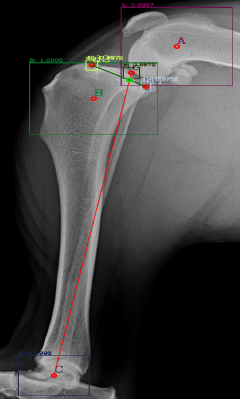

Following the identification of points of interests, and drawing of the lines of interest, i.e. the Functional Tibial Line (FTL) and the Medial Tibial Plateau Line (MTPL), another line is drawn such that the relation of new line and the FTL is 90°. Tibial plateau angle is the angle between this new line and the MTPL; this is shown in Fig. 3.

The dataset used for training was collected from various veterinary clinics, as none is available in the public domain, and the objects of interests were manually annotated. The resolution of these images vary largely as they are collected from various sources, thus for the sake of uniformity the images are all scaled to fit the same dimensions. The first part of this project was to develop a lightweight radiograph image sorting algorithm reported in [8]. The images chosen for the task described in this manuscript were all classified to be lateral lower body images by that sorting algorithm. Examples of manual annotations of objects of interests are given in Fig. 4: here regions A, B and C identify the joints while the point ’e’ identifies the centre of Talus and regions d1 and d2 identify the points that form the MTPL.

Most of the source dataset of over a thousand unique knee radiographs were distorted, had poor patient positioning, or were otherwise unfit for annotating. 250 of the original images were of sufficient quality to contribute to this effort. These images were set to have 6 different classes for training purposes, as mentioned and shown in Fig. 4. These were then trained using YOLOv3 [10] and the results of the predicted annotations are shown in Table I. From these predictions the centroids were extracted, which is then used to plot the FTL and MTPL. Then using the method mentioned in Section II, TPA is calculated. Examples of images, the region of interests detection and their respective TPA determination is shown in Fig. 6 and Table I: